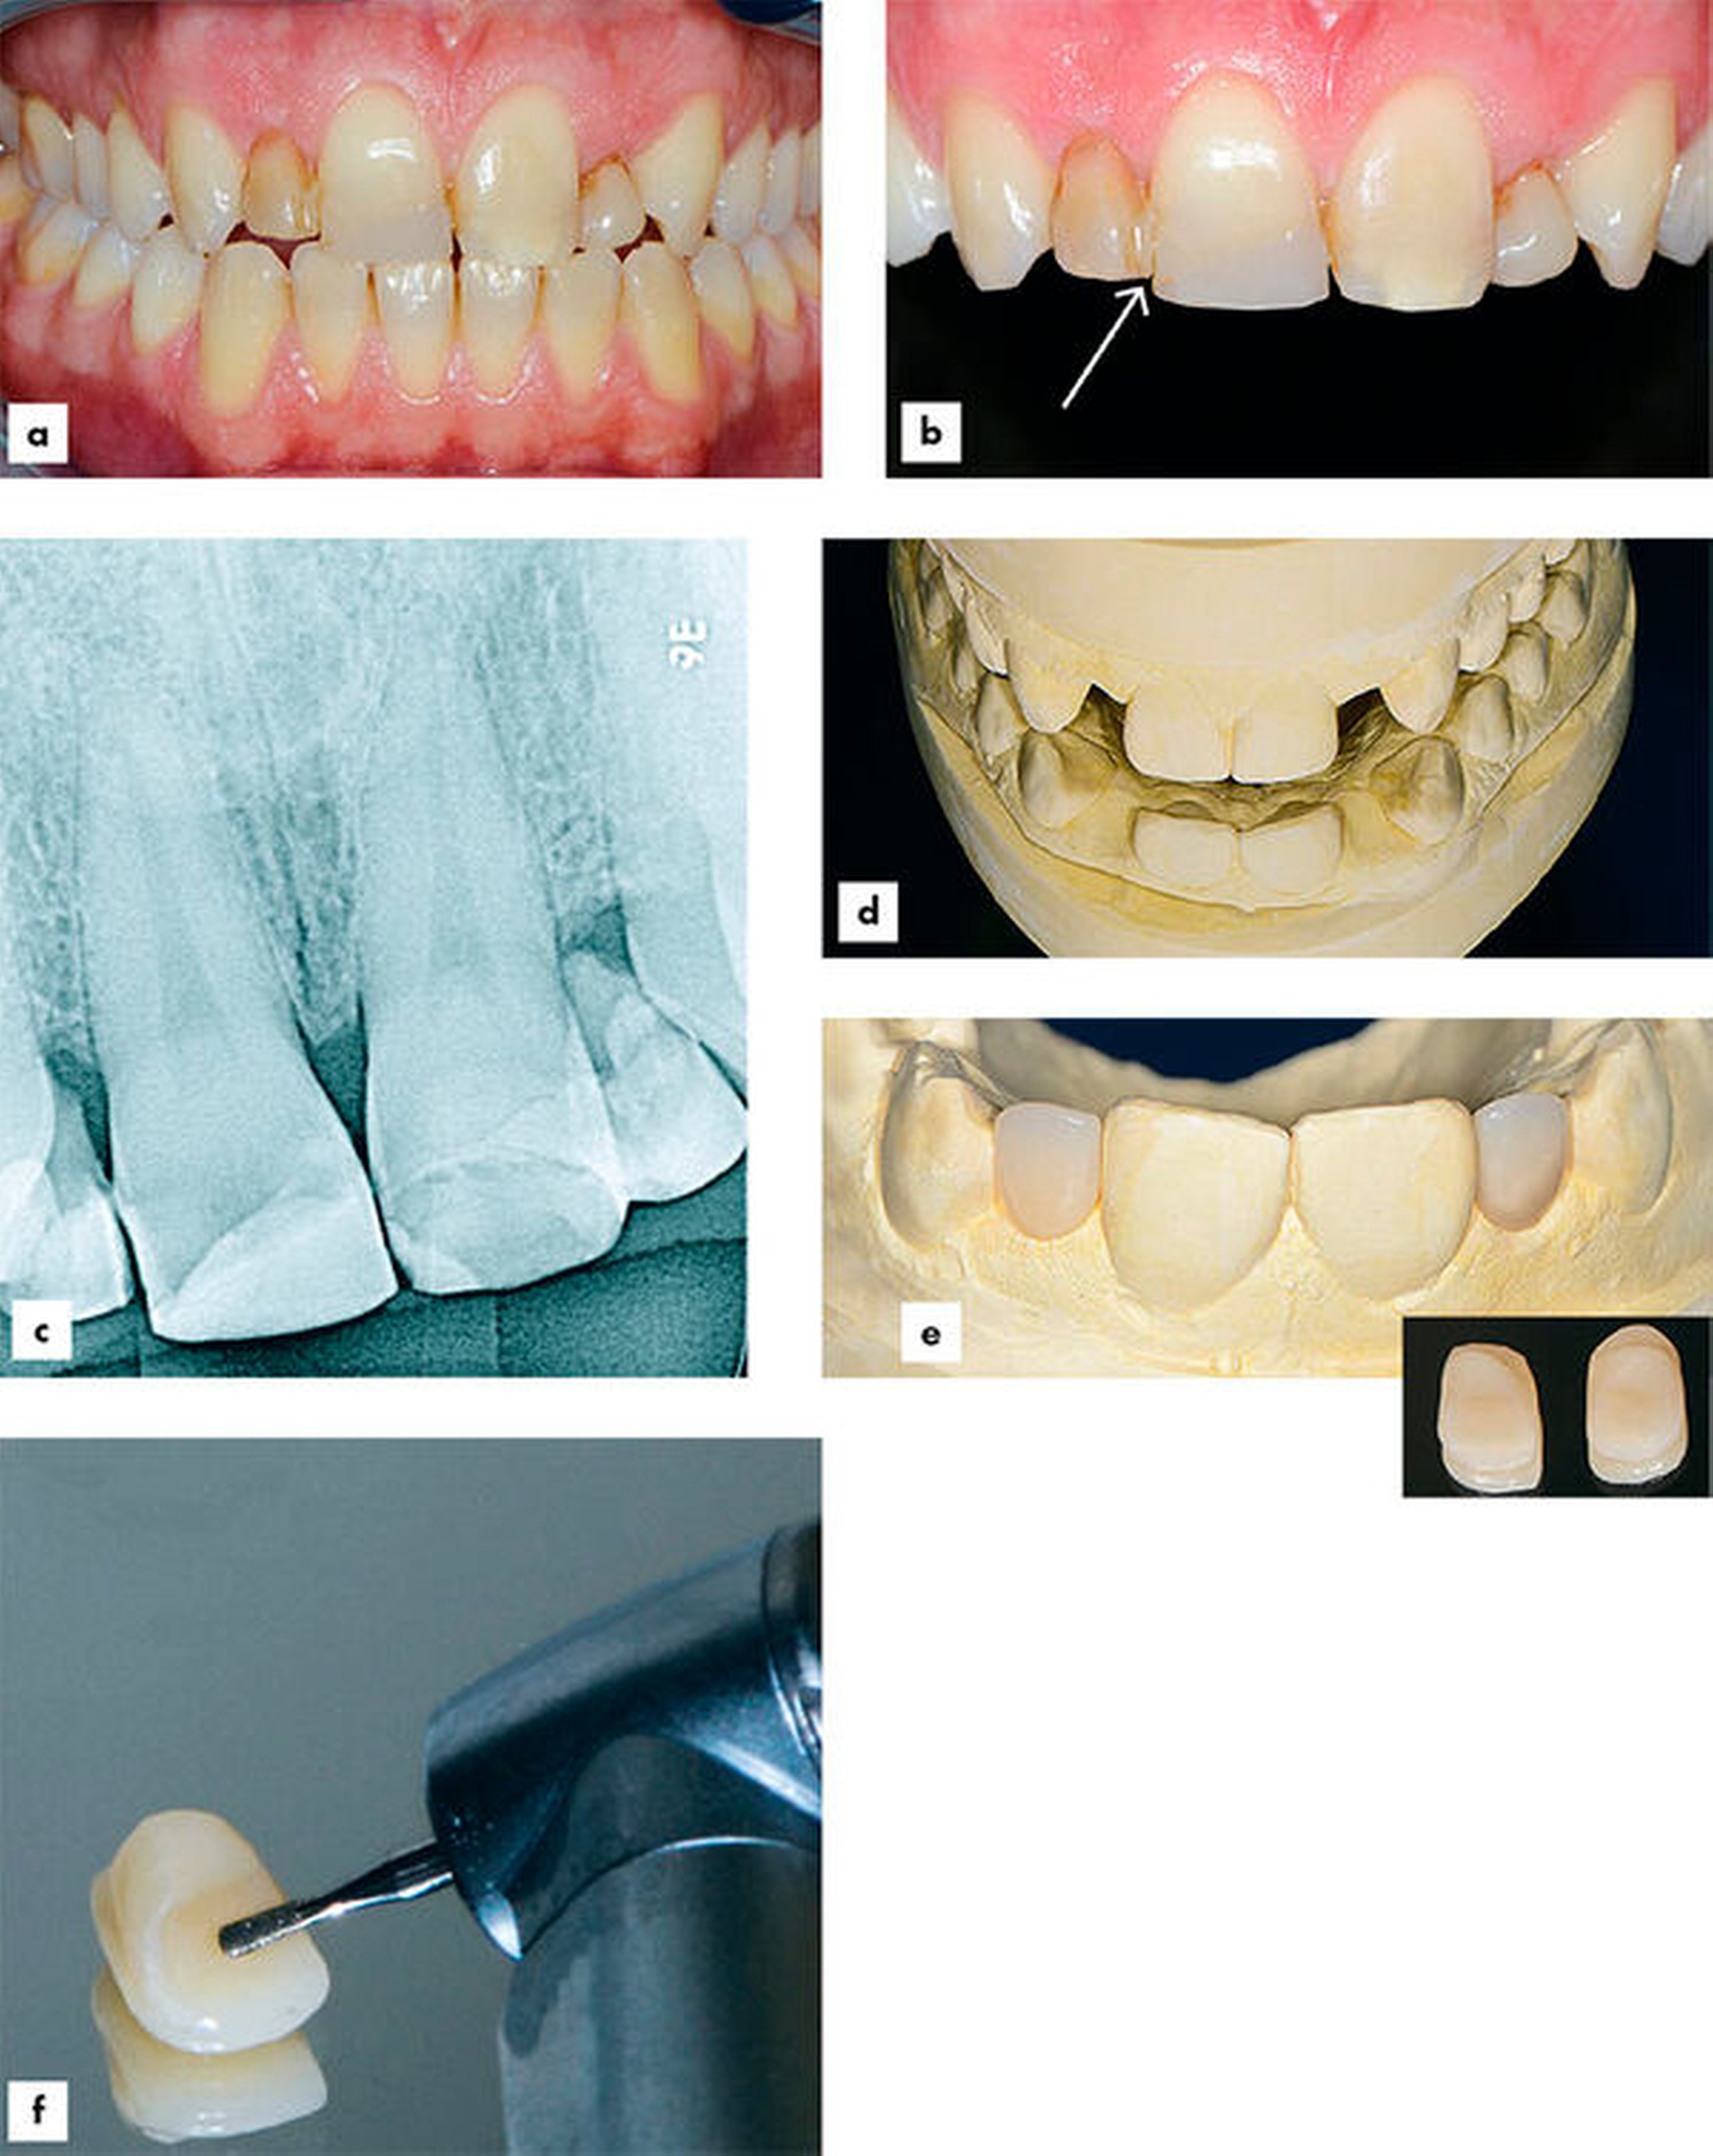

Ein 34-jähriger Lehrer stellte sich bei Nichtanlage der seitlichen Schneidezähne im Oberkiefer mit persistierenden Milchzähnen 52 und 62, die zur besseren Retention mittels Komposit mit den Zähnen 11 und 21 verblockt waren, in der Poliklinik für Zahnerhaltungskunde der Klinik für Mund-, Zahn- und Kieferkrankheiten des Universitätsklinikums Heidelberg vor (Abbildung 1a). Die Zähne 11 und 21 waren nach einem unkomplizierten Frontzahntrauma im Jugendalter mit Kompositrestaurationen versorgt worden. Bei der Erhebung der allgemeinen Anamnese gab der Patient keine Allgemeinerkrankungen an, er rauchte nicht und nahm keine Medikamente ein. Zum Zeitpunkt der Erstvorstellung hatte er keine Schmerzen und keine erhöhten Sondierungstiefen. Die Verblockung zwischen den Zähnen 11 und 52 war gebrochen und es bestand Lockerungsgrad II an Zahn 52 (Abbildung 1b, siehe Pfeil). Die Wurzeln der persistierenden Milchzähne 52 und 62 stellten sich bei röntgenologischer Abklärung als resorbiert dar. Der Röntgenbefund der Zähne 11 und 21 zeigte eine unauffällige periapikale Region sowie koronale Opazitäten im Sinne von Kompositrestaurationen. (Abbildung 1c). Die mesio-distale Breite der persistierenden Milchzähne 52 und 62 betrug circa 4 mm.

Die wichtigsten für die faserverstärkten Kompositbrücken verwendeten Materialien sind in Tabelle 2 aufgeführt. Es wurden Situationsmodelle hergestellt und die zu ersetzenden Milchzähne wurden auf dem Modell radiert (Abbildung 1d). Anschließend wurden zwei Pontics aus Komposit hergestellt (Abbildung 1e). Zur Aufnahme des faserverstärkten Kompositstrangs wurden in die palatinale Fläche der Pontics mit einem birnenförmigen Diamanten Rillen präpariert (Abbildung 1f) und die gesamte Palatinalfläche wurde mit Aluminiumoxidpulver (27 µm Korngröße) abgestrahlt. Da es die Okklusion erlaubte, mussten die Pfeilerzähne 11 und 21 palatinal nicht präpariert werden.